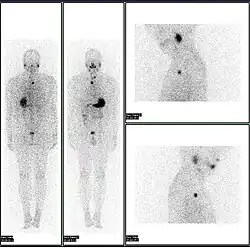

A nuclear medicine whole body bone scan. The nuclear medicine whole body bone scan is generally used in evaluations of various bone-related pathology, such as for bone pain, stress fracture, nonmalignant bone lesions, bone infections, or the spread of cancer to the bone.

A nuclear medicine whole body bone scan. The nuclear medicine whole body bone scan is generally used in evaluations of various bone-related pathology, such as for bone pain, stress fracture, nonmalignant bone lesions, bone infections, or the spread of cancer to the bone. -